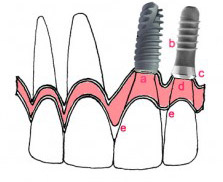

این مدل از انواع ایمپلنت یکی از رایجترین مدلها است. به لحاظ اینکه برای عملهای دو مرحلهای طراحی شده و تا به امروز نیز شاهد کارایی مطلوب آن هستیم. ایمپلنتهای اندواستیل به شکل پیچهای کوچک و از جنس تیتانیوم ساخته شدهاند. نحوه نصب آن نیز بدین صورت است که ابتدا پیچهای تیتانیومی درون استخوان فک قرار داده شده و سپس دندانهای مصنوعی روی این پایهها متصل میگردد.

این سری از انواع ایمپلنت برخلاف ایمپلنتهای اندواستیل درون استخوان فک قرار نمیگیرد. در واقع هنگام کاشت ایمپلنت ساب پریواستیل مقداری از پایههای تیتانیومی درون لثه قرار گرفته و بخشی از آن نیز بیرون میماند. تا دندان های مصنوعی بر پایه ایمپلنت بر روی آن نصب شده و بدین نحوه فرآیند کاشت ایمپلنت به پایان برسد. به عبارت دیگر در ایمپلنت ساب پریواستیل هیچگونه شیار و شکافی در استخوان فک ایجاد نمیشود و دندان صرفاً درون لثه قرار میگیرد. خاطر نشان میشود که این روش برای افرادی کاربرد دارد، که تراکم استخوان فک آنها بسیار ضعیف است و امکام پیوند استخوان از طریق جراحی وجود ندارد. بدین ترتیب اگر جزء این دسته از افراد هستید، توصیه میکنیم حتماً از این نوع ایمپلنت استفاده کنید.

به طور کلی ایمپلنت یک نوع دندان کاشتنی است. که از نظر ساختار و ظاهر شباهت زیادی با دندانهای طبیعی دارد و علاوه بر افزایش قدرت جویدن مواد خوراکی، زیبایی ظاهر و جذابیت لبخند را برای افراد به ارمغان میآورد. این دندان کاشتنی معمولاً از جنس تیتانیوم میباشد و درون استخوان فک قرار میگیرد. بدین نحو که پس از کشیدن دندانهای خراب، یک سوراخ یا شیار درون لثه و استخوان فک ایجاد میکنند. سپس پایه ایمپلنت تیتانیومی که به آن فیکسچر ایمپلنت هم میگویند درون آن قرار داده میشود. در پایان نیز پس از جوش خوردن کامل استخوان فک با پایه ایمپلنت، تاج ساخته شده در لابراتورهای دندانپزشکی روی آن قرار داده میشود.